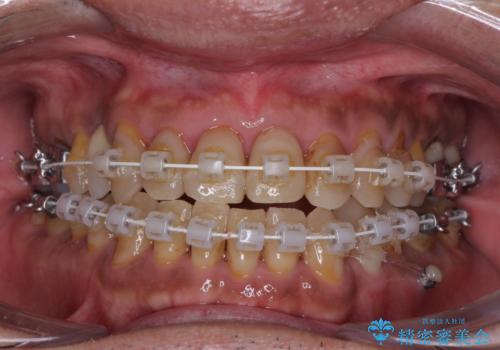

今からでも綺麗な歯並びを手に入れたい 40代男性のワイヤー矯正

- 審美装置

- 前歯のクロスバイトを気にして来院された患者様です。

40代男性で、インプラント補綴治療も経験されている方で、矯正治療をしても良いのかと悩んでいらっしゃいました。

下顎骨の左右のずれがあり、下顎全体が前方に出ている状態であったので、無理をせずにワイヤー装置にて矯正治療を行うこととしました。

クロスバイト改善には難儀しましたが、咬みやすく、笑ったときに清潔感ある口元に仕上げることができました。